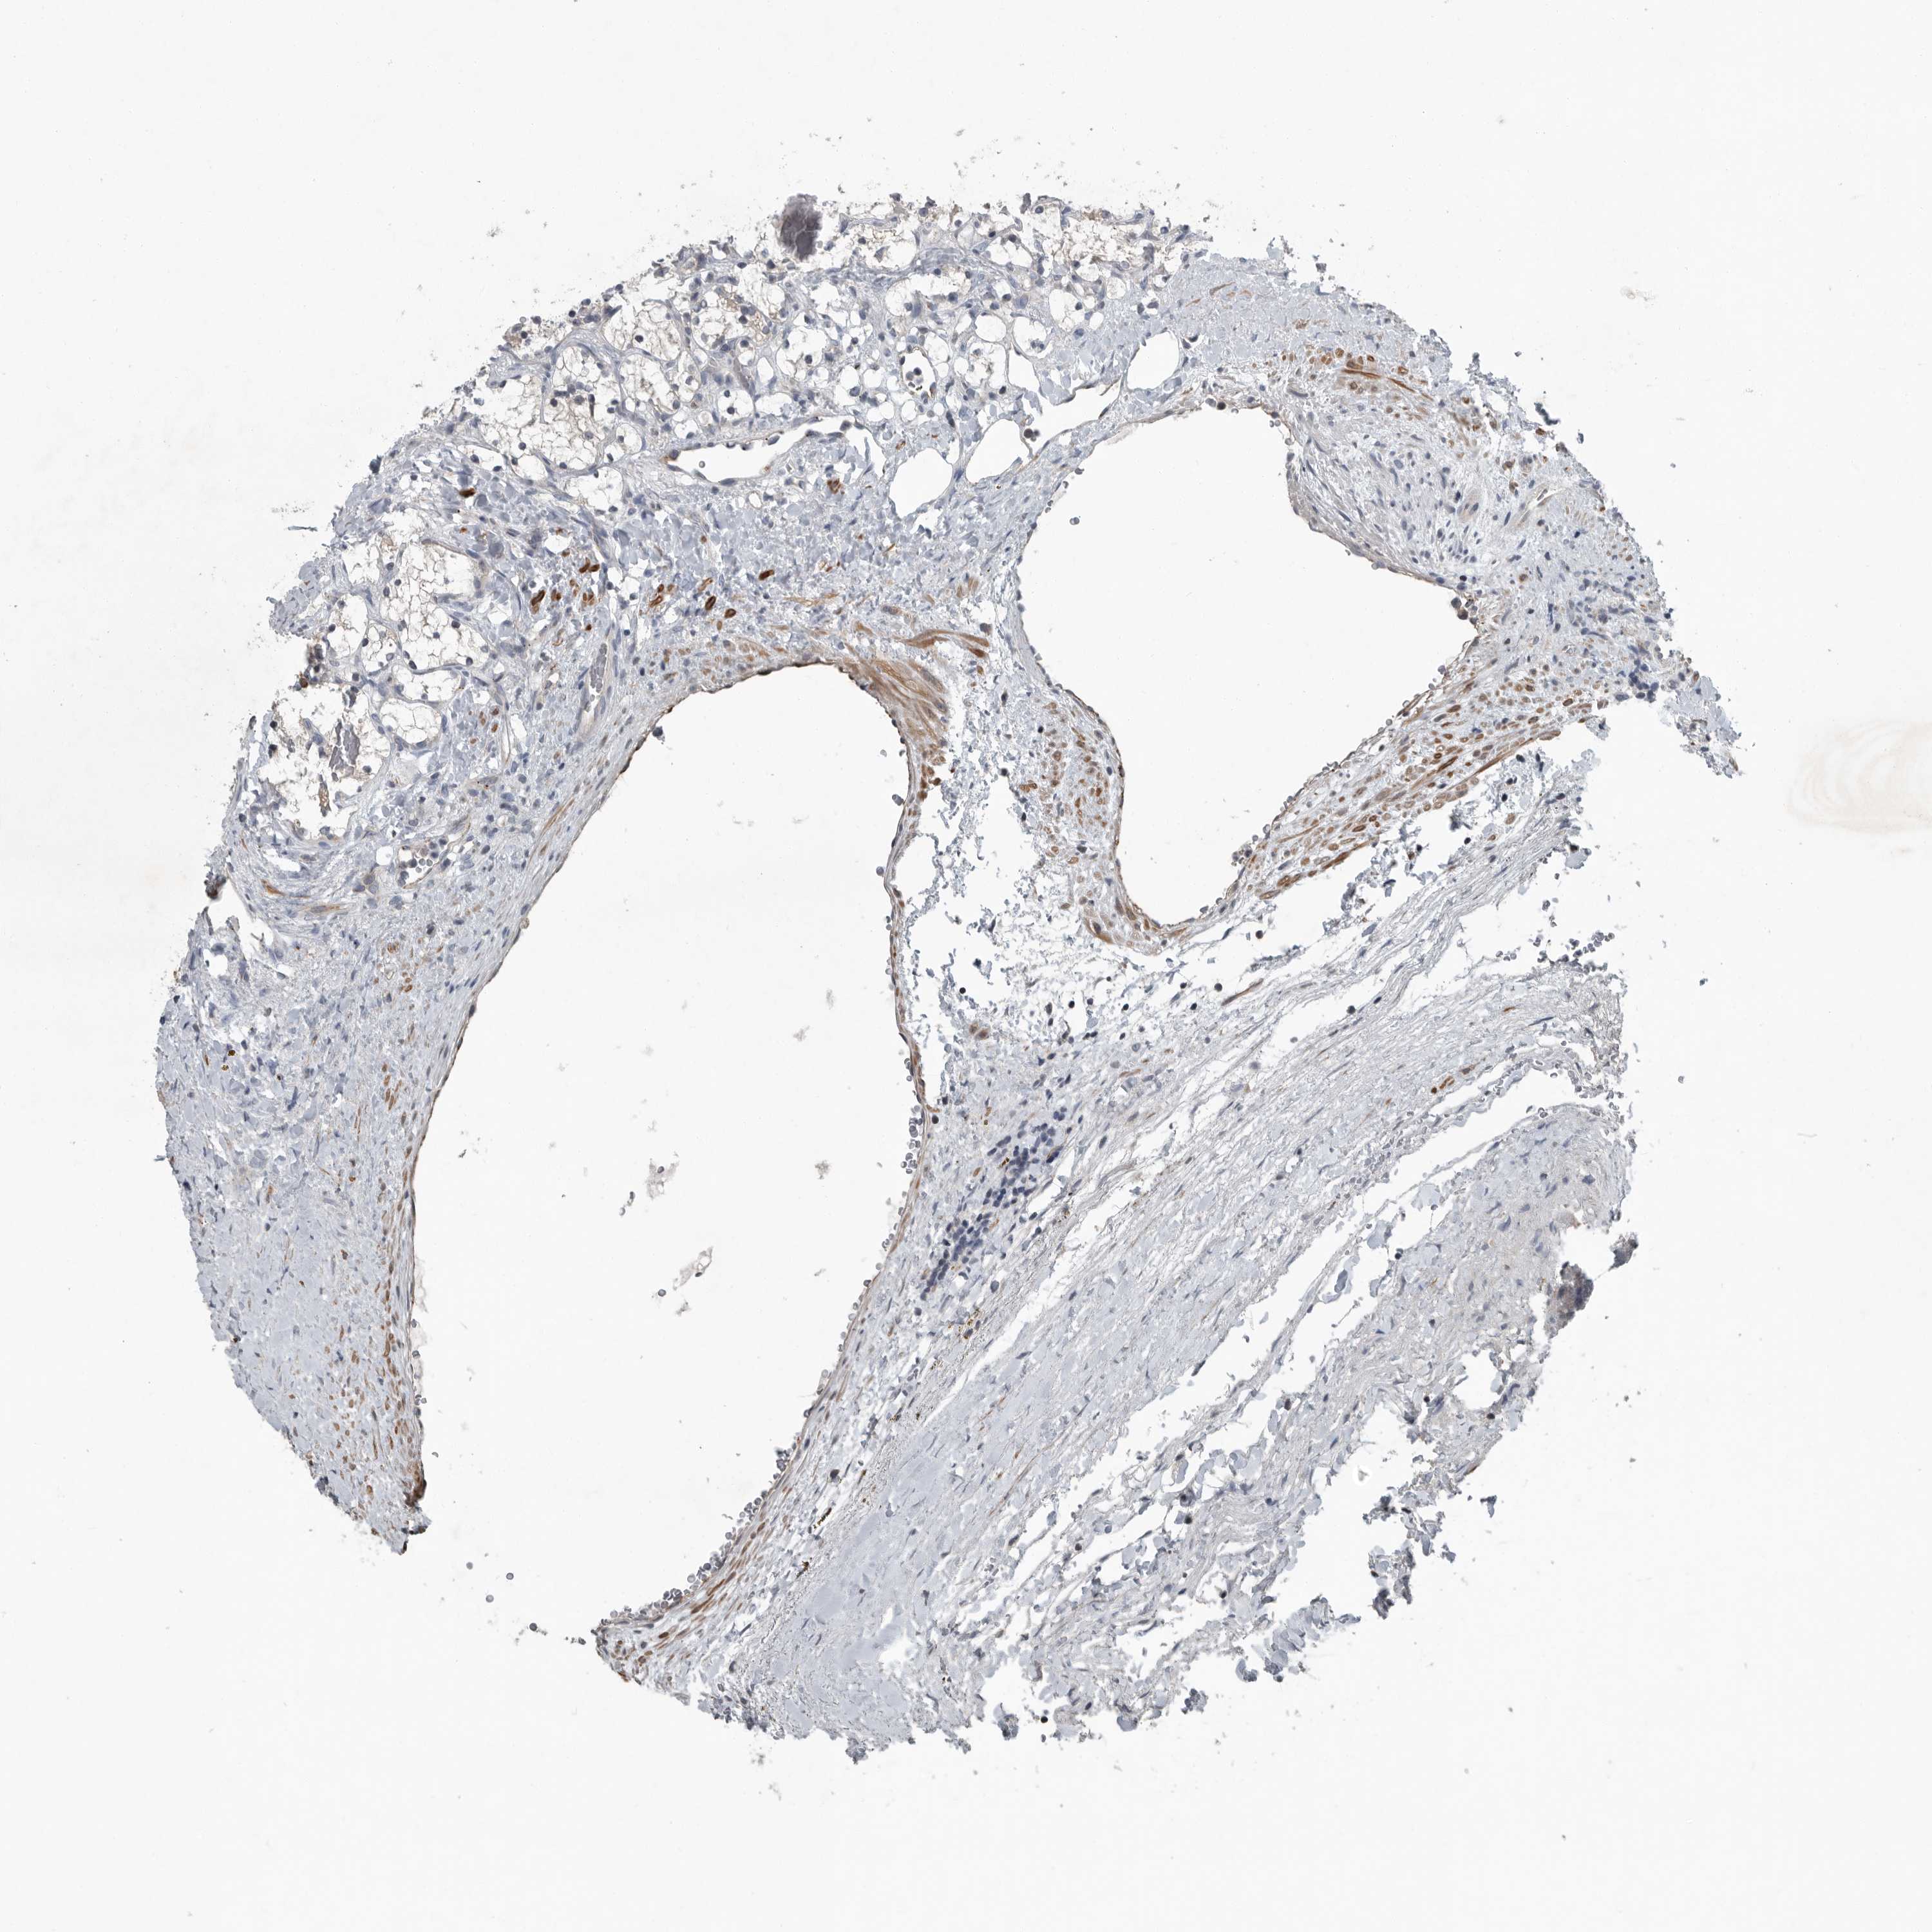

CANCER RENAL CANCER Show tissue menu

KICH TCGA KIRC TCGA KIRC VALIDATION KIRP TCGA PROTEIN RCC CPTAC PROTEIN EXPRESSION